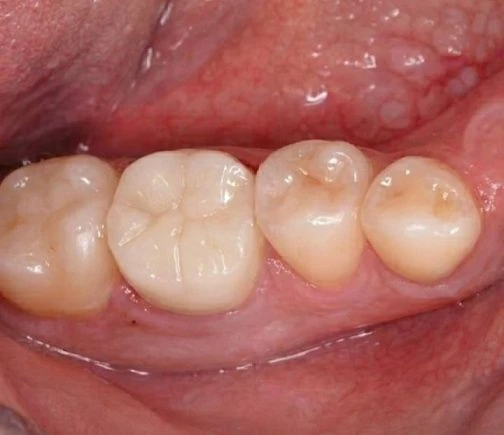

Наши специалисты внимательно подходят к подготовке и подбирают оттенок коронки, идеально повторяющий натуральную эмаль пациента. При правильном изготовлении и установке отличить искусственную коронку от натурального зуба невозможно, и удается полностью восстановить эстетику улыбки.

Наши работы